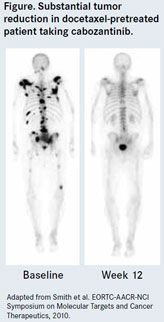

Sartor also discussed cabozantinib (XL184), a small molecule designed to inhibit multiple receptor tyrosine kinases, specifically MET and vascular endothelial growth factor receptor-2 (VEGFR-2). MET is a receptor tyrosine kinase that plays key roles in cellular proliferation, migration, and invasion, as well as in angiogenesis. It is highly expressed in prostate bone metastases. Docetaxel-pretreated patients have experienced substantial tumor reduction during therapy with cabozantinib, 12 weeks after the agent was introduced. While one patient does not tell the entire story, Sartor said that a whole series of patients have experienced similarly promising results in clinical trials. A phase 2 clinical trial is now recruiting adults with advanced malignancies.